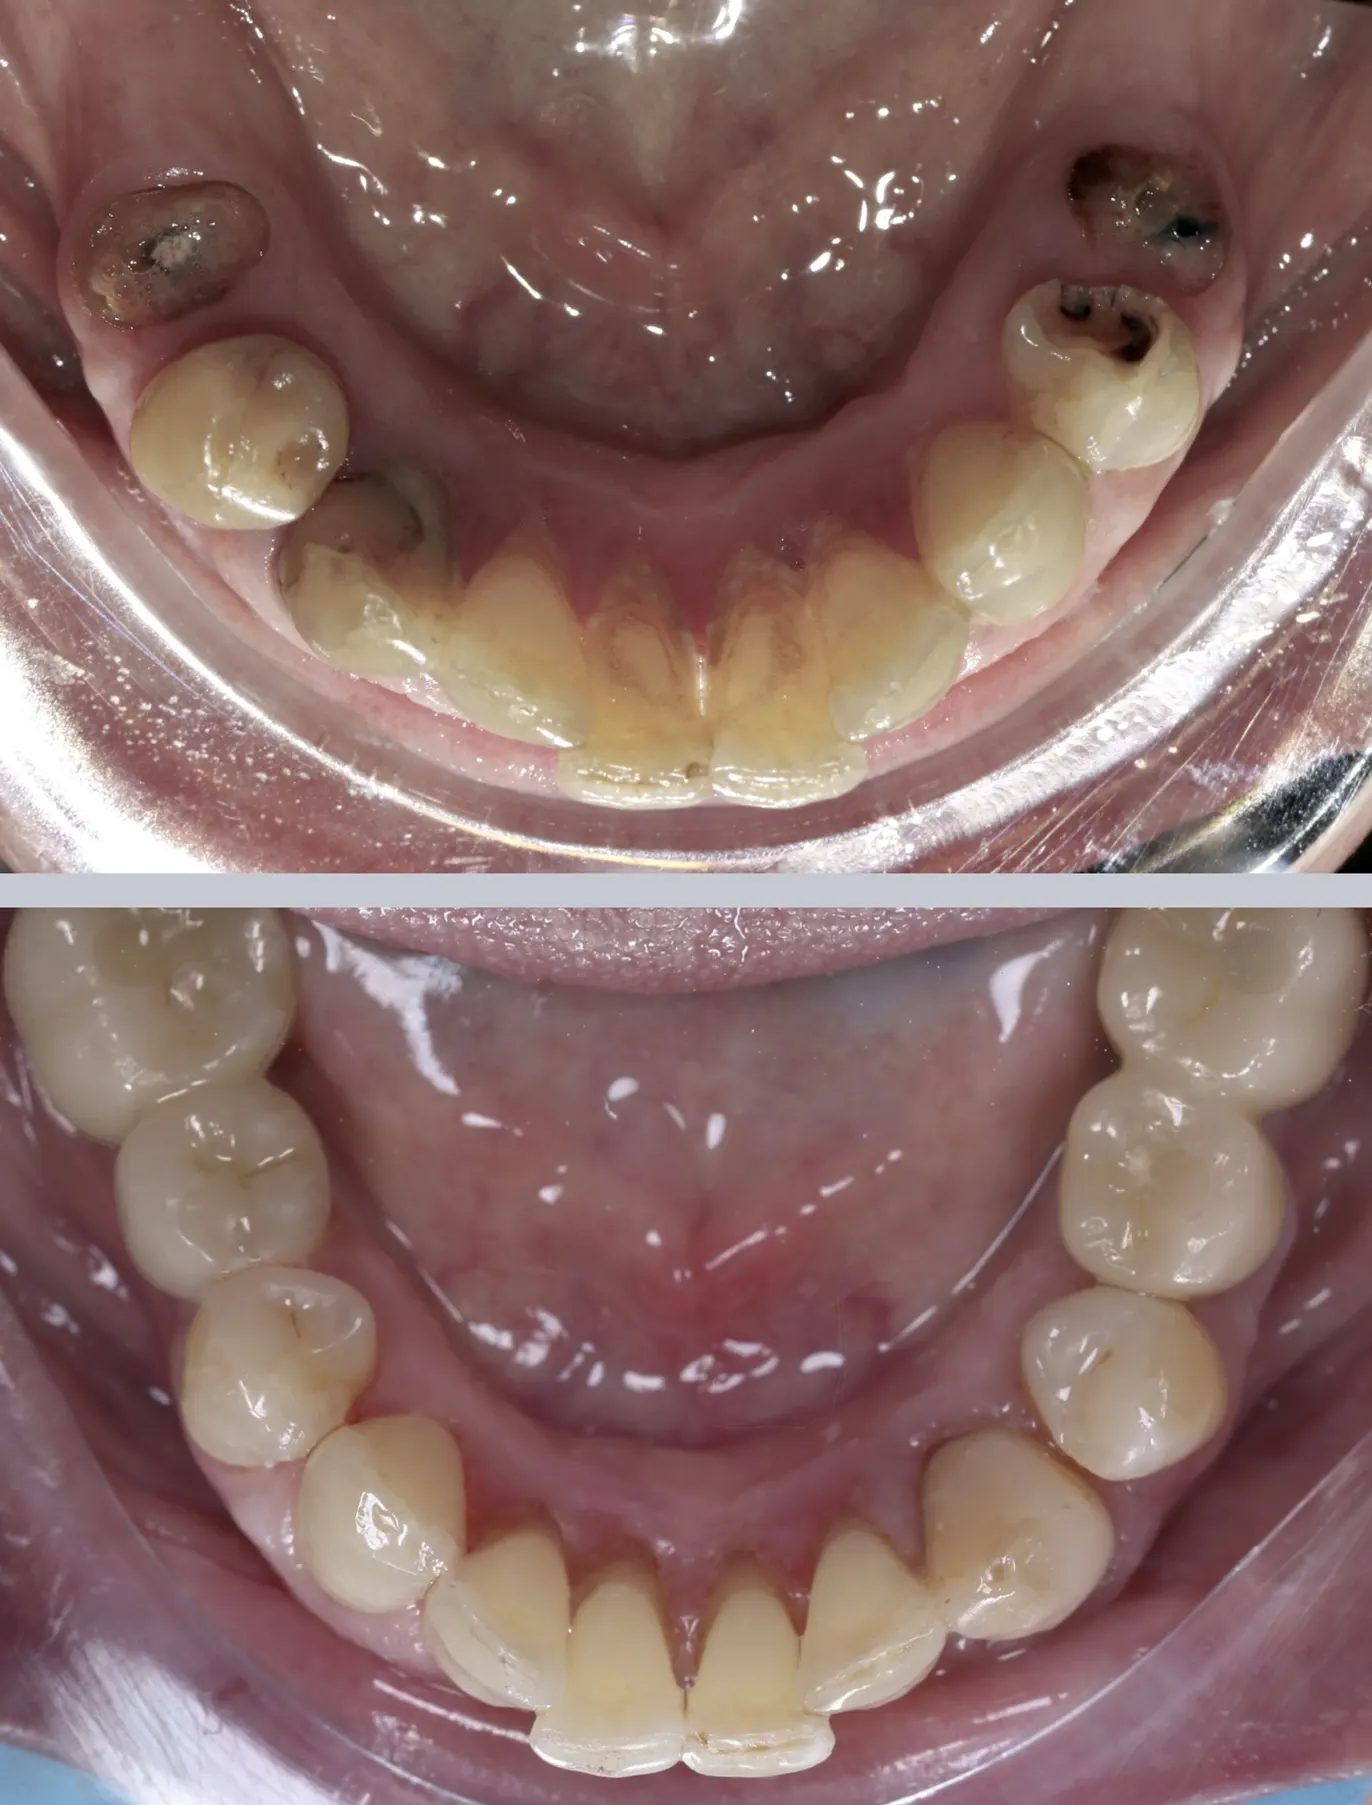

Пациент обратился с выраженными разрушениями зубов в боковых отделах нижней челюсти и отсутствием нескольких моляров. На первичной консультации выявлен глубокий кариес, который повлек за собой разрушение коронковой части, потемнение эмали и неудовлетворительное состояние зубов, что не только портило внешний вид, но и затрудняло полноценное пережёвывание пищи. Нагрузка распределялась неравномерно, из-за чего оставшиеся зубы испытывали повышенное давление. Ситуация доставляла дискомфорт в повседневной жизни и ограничивала выбор пищи.

На первом этапе была проведена профессиональная гигиена полости рта для подготовки к комплексному лечению. Далее выполнено лечение кариеса и терапевтическое восстановление сохранённых зубов. В боковых отделах проведена хирургическая имплантация с установкой имплантатов для последующего восстановления утраченных зубов.

После периода приживления выполнено протезирование на имплантатах с целью восстановления анатомической формы зубов и полноценной функции жевания.

В результате лечения полностью восстановлена эстетика, эффективность и целостность нижней челюсти. Зубной ряд выглядит естественно, гармонично и анатомически правильно, жевательная нагрузка распределяется равномерно.